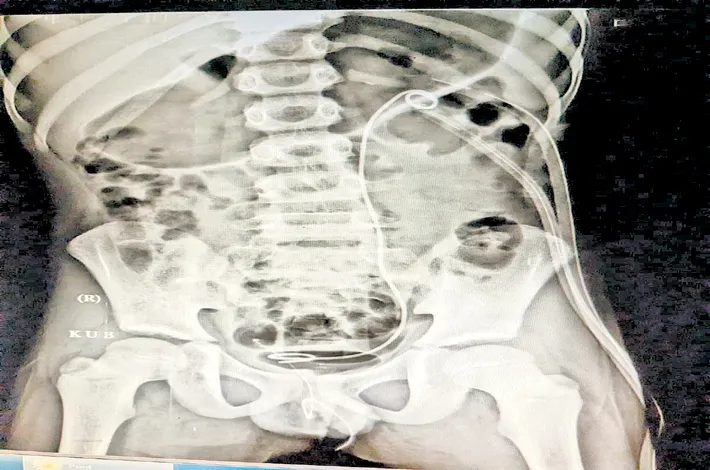

హైదరాబాద్ సిటీ బ్యూరో, నవంబర్ 26 (విజయక్రాంతి): వరంగల్ ప్రాంతానికి చెందిన ఎనిమిదేళ్ల బాలుడికి ఎడమవైపు కిడ్నీ నిండా రాళ్లు ఏర్పడటంతో అతడిని హైదరాబాద్ బంజారాహిల్స్లోని ఏషియన్ ఇనిస్టిట్యూట్ ఆఫ్ నెఫ్రాలజీ అండ్ యూరాలజీ (ఏఐఎన్యూ)కు తీసుకొచ్చారు. ఇందుకు సంబంధించిన వివరాలు, పిల్లల్లో కిడ్నీ రాళ్ల సమస్యల గురించి ఏఐఎన్యూకు చెందిన కన్సల్టెంట్ పీడియాట్రిక్, ట్రాన్సిషనల్ యూరాలజిస్ట్ డాక్టర్ పి.అశ్విన్ శేఖర్ ఇందుకు సంబంధించిన వివరాలు తెలిపారు.

‘బాలుడిని ఇక్కడకు తీసుకురాగానే సమస్యను గుర్తించి, పెర్క్యుటేనియస్ నెఫ్రో లితోటమీ (పీసీఎన్ఎల్) చేయాలని నిర్ణయించాం. ఇందులోభాగంగా వీపు భాగంలో చిన్న రంధ్రం చేసి, నెఫ్రోస్కోప్ ద్వారా కిడ్నీలోకి వెళ్లి ఎక్కువ నొప్పి లేకుండా రాళ్లను తొలగించాం. అత్యాధునిక సాంకేతికను ఉపయోగించడం ద్వారా ఒక పెద్దరాయి, మరికొన్ని చిన్నరాళ్లు అన్నింటినీ ఒకే సిటింగ్లో తొలగించాం. సంప్రదాయ శస్త్రచికిత్సల కంటే ఇందులో త్వరగా కోలుకుంటారు. దీనివల్ల ఆస్పత్రిలో ఉండాల్సిన సమయం తగ్గుతుంది’ అన్నారు. రోజుకు కనీసం లీటరున్నర మూత్రం పోయేలా నీళ్లు తాగాలని సూచించారు. అలా తాగకపోతే మూత్రం చిక్కబడుతుంది. అదే కిడ్నీలో రాళ్లు ఏర్పడడానికి సూచిక అన్నారు.